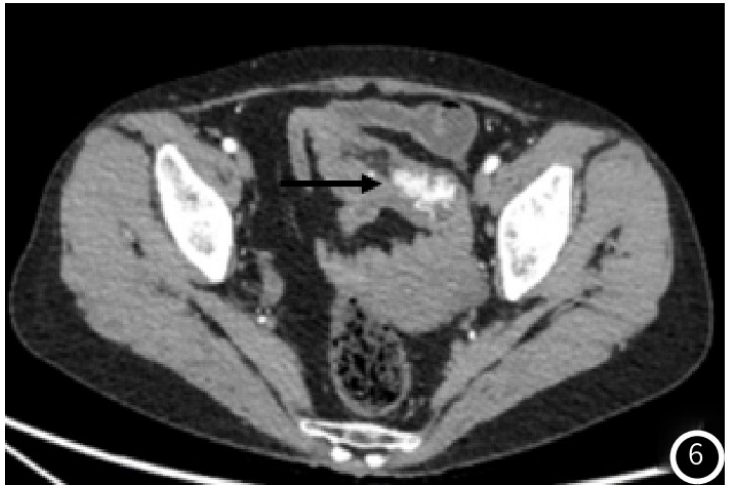

示胰头类圆形低密度结节,大小约14mm×12mm,增强扫描动脉期结节明显均匀强化(图1),强化程度高于正常胰腺实质,静脉期强化减低,边界清;术后4年常规胸腹部CT

图6 盆腔团片状软组织影,包绕腹腔内脂肪及血管,增强见片状明显强化(黑箭头);